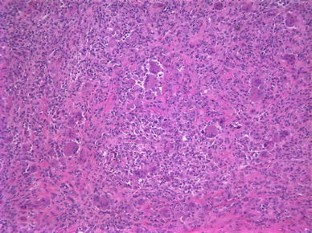

Soft tissue giant cell tumor of low malignant potential is a rare tumor located in superficial and deep soft tissue. Tumors with osteoclast-like giant cells have been reported in various sites as breast, salivary glands, lung, kidney and pancreas. These tumors are composed of evenly spaced multinucleated giant cells in a background of mononuclear component composed of round, oval or spindled cells. No atypia or significant mitotic activity is encountered. Immunohistochemical stains for TRAP, smooth muscle actin, desmin and cytokeratins are of great value for diagnosis. Nasal cavity represents a very unusual location for this type of tumors; soft tissue tumors must be included in the differential diagnosis of nasal obstruction. Due to the possibility of local recurrence, clinical follow-up is recommended.

Fig. 1